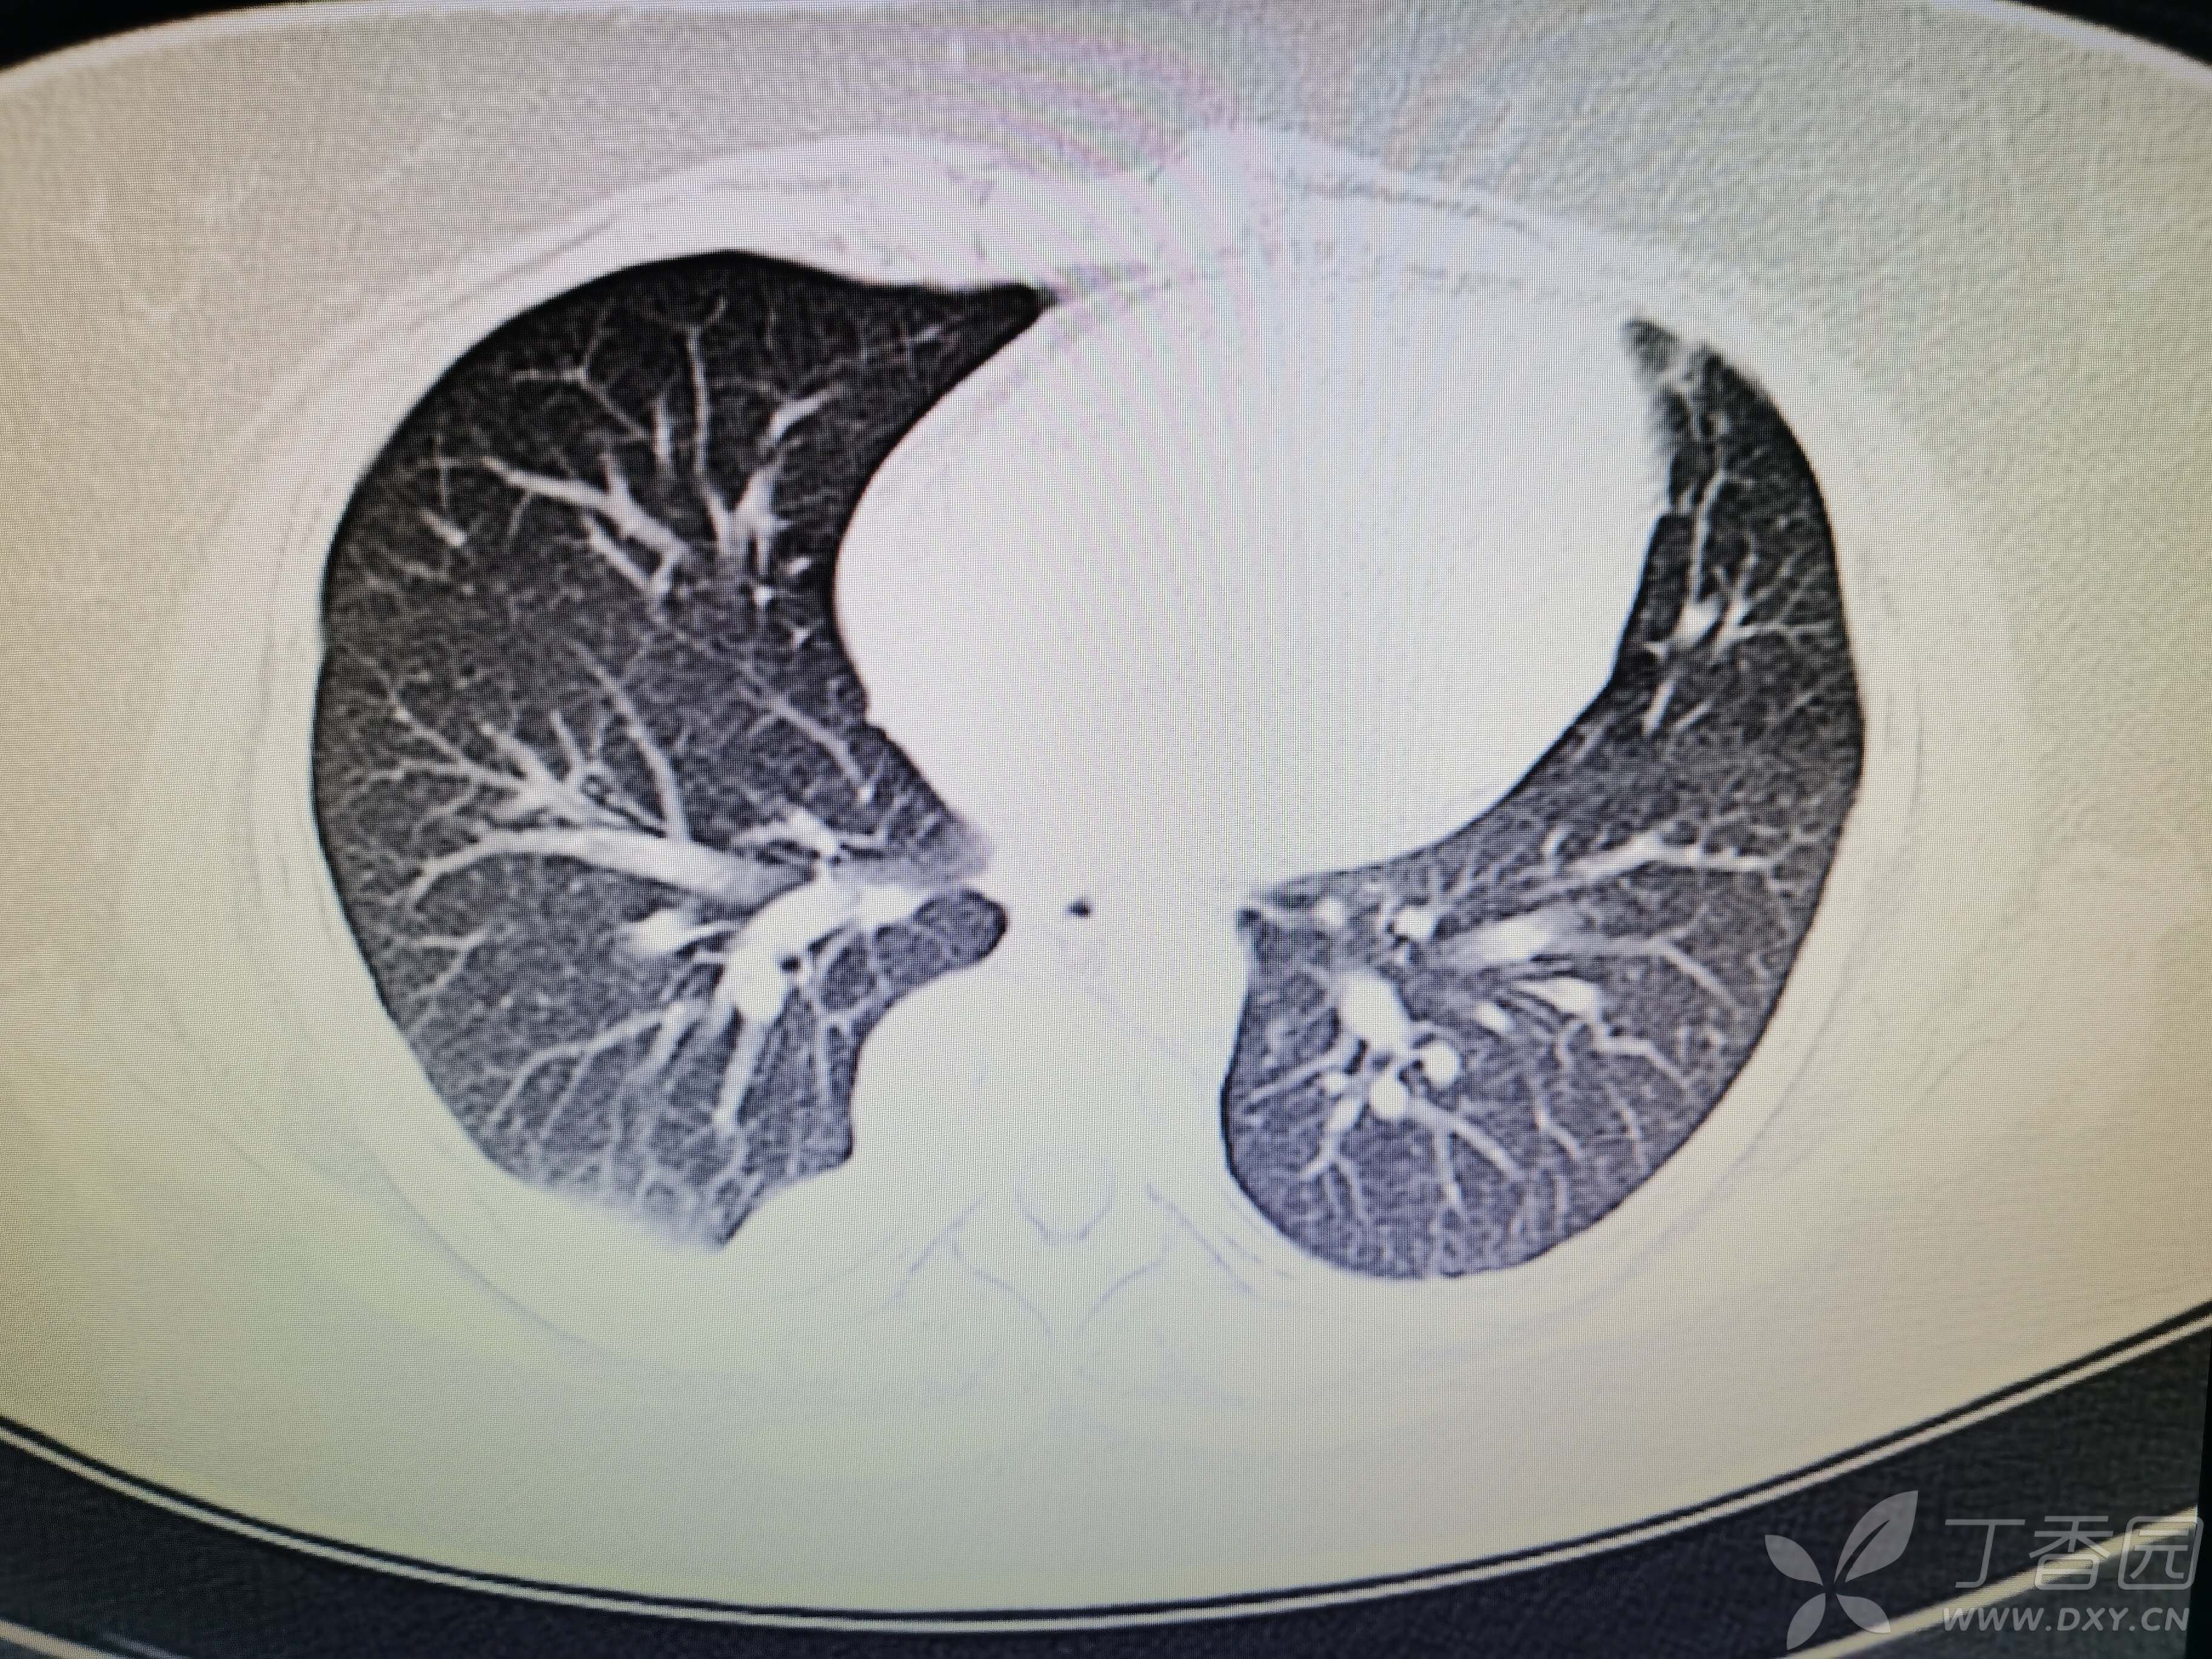

基本信息:女,三十几岁,印度人。。

胸部CT:

如题:猜肺部病灶病理。。